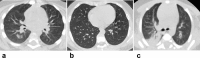

Findings: Compared with the non-pregnant adults group (n = 14), initial normal body temperature (9 [56%] and 16 [64%]), leukocytosis (8 [50%] and 9 [36%]) and elevated neutrophil ratio (14 [88%] and 20 [80%]), and lymphopenia (9 [56%] and 16 [64%]) were more common in the laboratory-confirmed (n = 16) and clinically-diagnosed (n = 25) pregnant groups. Totally 614 lesions were detected with predominantly peripheral and bilateral distributions in 54 (98%) and 37 (67%) patients, respectively. Pure ground-glass opacity (GGO) was the predominant presence in 94/131 (72%) lesions for the non-pregnant adults. Mixed consolidation and complete consolidation were more common in the laboratory-confirmed (70/161 [43%]) and clinically-diagnosed (153/322 [48%]) pregnant groups than 37/131 (28%) in the non-pregnant adults (P = 0·007, P < 0·001). GGO with reticulation was less common in 9/161 (6%) and 16/322 (5%) lesions for the two pregnant groups than 24/131 (18%) for the non-pregnant adults (P = 0·001, P < 0·001). The pulmonary involvement in children with COVID-19 was mild with a focal GGO or consolidation. Twenty-three patients underwent follow-up CT, revealing progression in 9/13 (69%) at 3 days whereas improvement in 8/10 (80%) at 6-9 days after initial CT scans.

Interpretation: Atypical clinical findings of pregnant women with COVID-19 could increase the difficulty in initial identification. Consolidation was more common in the pregnant groups. The clinically-diagnosed cases were vulnerable to more pulmonary involvement. CT was the modality of choice for early detection, severity assessment, and timely therapeutic effects evaluation for the cases with epidemic and clinical features of COVID-19 with or without laboratory confirmation. The exposure history and clinical symptoms were more helpful for screening in children versus chest CT.